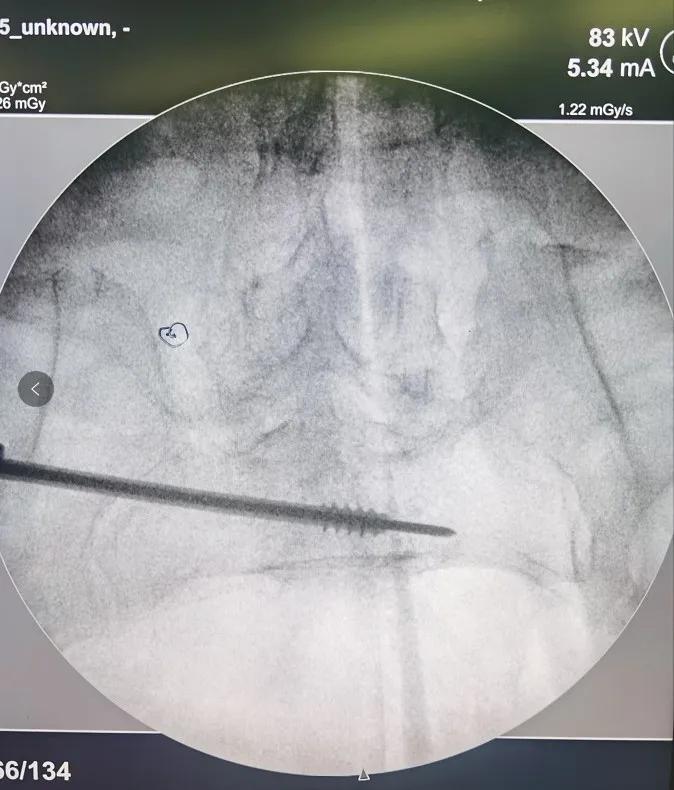

术中影像